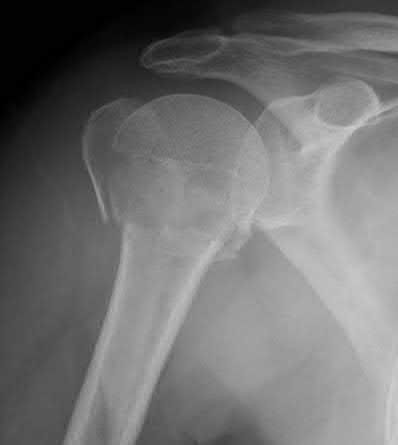

Question 11:

A poly-trauma patient presents hemodynamically unstable with an anteroposterior compression (APC-III) pelvic ring injury. A circumferential pelvic binder is requested to reduce pelvic volume and control hemorrhage. To be anatomically effective, the binder must be centered precisely over which of the following landmarks?